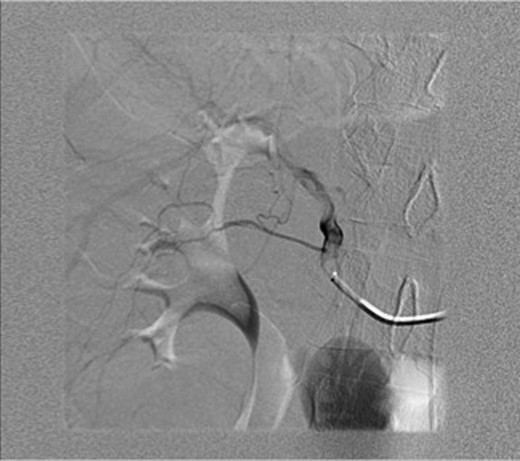

An ultrasound was done showing a mass in the right upper quadrant with no visualization of the gallbladder and no evidence of biliary tree dilatation. Therefore, a CT scan was performed which showed a large haematoma in the gallbladder fossa, which distends the gallbladder wall causing mass effect (Fig. 1a and b). Furthermore, active extravasation of IV contrast was seen. Initially, this was not clear if the haematoma is arising from the liver or within the gallbladder. Given his haemodynamic stability he was taken to the interventional angiography suite for an arteriogram of his abdominal aorta and splanchnic vessels. The bleeding was localized to a branch of the cystic artery and no pseudoaneurysm was identified (Fig. 2). Then, embolization of cystic artery with gelfoam material was performed. Since, embolization of the cystic artery proper was done, the decision was made to explore the patient and perform a cholecystectomy. Prior to the operation the patient became tachycardic at 100 with a systolic blood pressure of 90 and a diastolic of 60. His repeat haemoglobin was 10.1. Appropriate resuscitation with blood transfusion was performed.

(a and b) CT scan upper abdomen showing a large haematoma in the gallbladder fossa, which distends the gallbladder wall causing mass effect.

Arteriogram of abdominal aorta and splanchnic vessels showing localized bleeding in a branch of the cystic artery and no pseudoaneurysm.